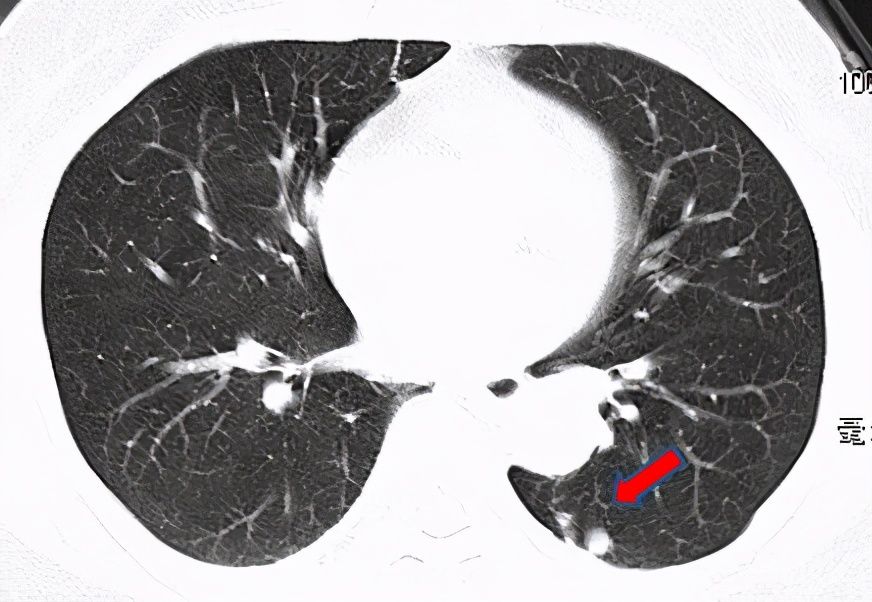

隐球菌【 结节|刀下“留肺”!容易误认为癌性“肺结节”的8种感染】王伯伯退休之后,生活特别滋润:每天喂养鸽子,逛逛公园,感觉人生巅峰也不过如此。最近他有点咳嗽,虽然不严重,但就是一直不好转,孝顺的儿子非要他去检查下,王伯伯直到拿到报告前还嘟囔他小题大做,直到报告上“左下肺结节”这五个字吓坏了他。

辗转多次就医,儿子带着王伯伯来到了中山医院感染病科,医生仔细看了片子,又详细问了王伯伯的日常生活,当听说他家里有几只宝贝鸽子的时候,医生的眼睛biu~地亮了:估计就是这货惹的!医生安排了CT引导下肺穿刺,第二天病理检查结果就出来了:考虑隐球菌感染。

医生介绍说,隐球菌是一种真菌,我国的隐球菌感染多与鸽子、鸽粪有关,药物疗效大多满意,但是继续养鸽子可能还会感染其他人。无奈之下,王伯伯遣散了“鸽子军团”,经过几个月的抗真菌,肺结节完全吸收了,一家人终于松了口气。王伯伯说,其实电视里看看鸽子也挺好,距离产生美。